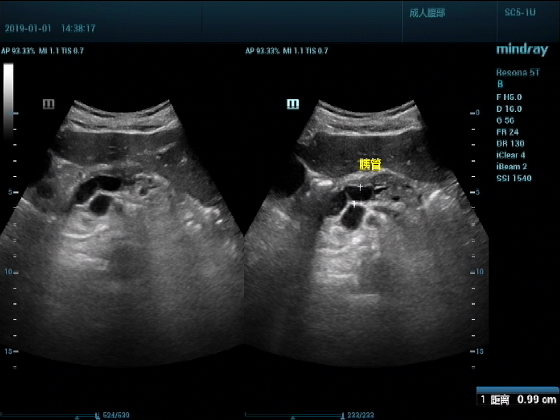

超声入门贴959--胰头癌并胰管扩张

男,88岁,腹部隐疼2个月加重3天来诊

胰腺显示的很清楚,图像清晰